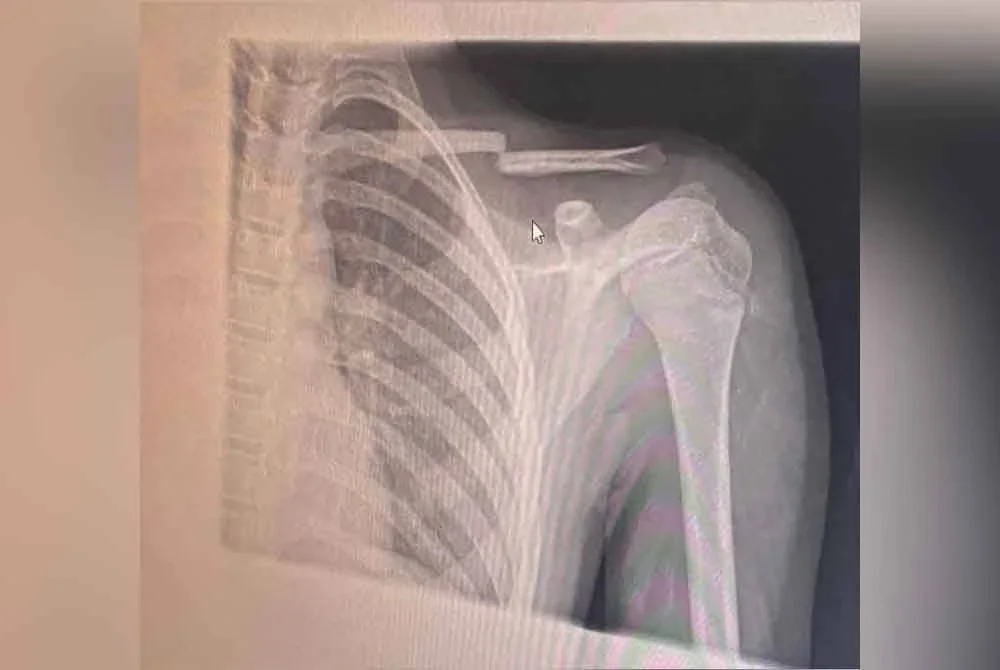

KAJANG - Patah tulang selangka merupakan kemuncak kejadian buli dialami seorang kanak-kanak lelaki berusia 12 tahun di sebuah sekolah rendah agama di sini.

“Tapi insiden sehingga patah tulang selangka ini terlalu serius. Saya buat laporan polis dan pegawai penyiasat datang ke sekolah, ambil keterangan guru besar, guru kelas, beberapa saksi dan ibu bapa,” katanya kepada Sinar Harian.